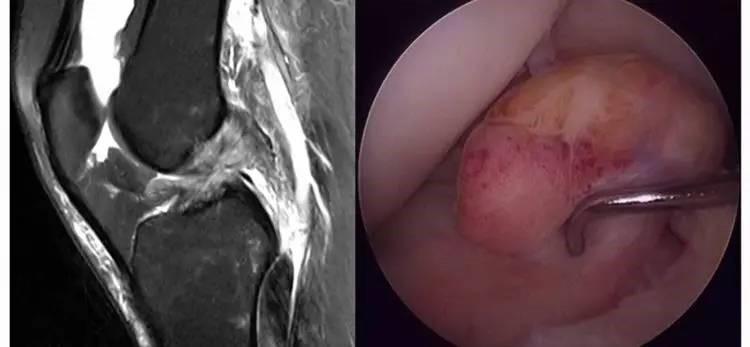

6.扭曲和空虚:髁间窝内似隐隐约约有低信号,边缘明显,中央空虚;或者中央有低信号,但扭曲如麻花状。多为陈旧损伤,仅存ACL的滑膜,里面可有少量的韧带纤维,粘附在后方,随着膝关节的长时间屈伸逐渐呈扭曲状。

13.gif